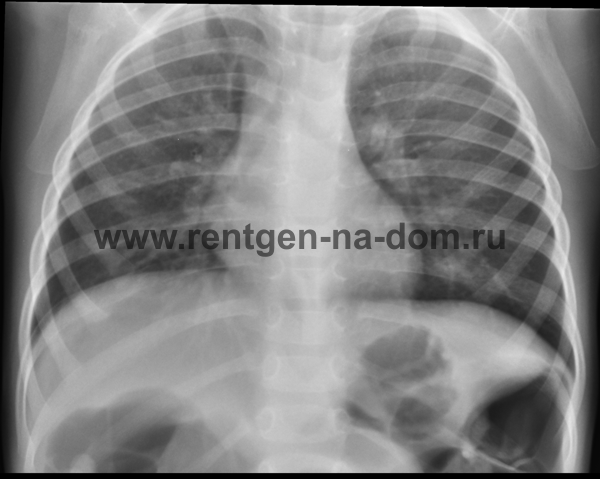

Наиболее частой причиной, по которой врачи различных специальностей, в первую очередь врачи терапевты поликлиник, назначают рентген легких, является подозрение на пневмонию.

Пневмония – простыми словами воспаление легких – острое воспаление легочной ткани инфекционного происхождения с преимущественным поражением альвеол и интерстициальной ткани легкого. При этом жидкость скапливается в просвете альвеол, что ведет к уменьшению дыхательной поверхности легких. Пневмония может быть самостоятельным заболеванием или быть осложнением другого. Заподозрить пневмонию можно при аускультации (выслушивании) легких при дыхании. Поздняя диагностика и задержка с началом антибактериальной терапии ухудшают прогноз заболевания, возможен летальный исход. Поэтому при малейших подозрениях необходимо сделать рентген легких, особенно пожилым пациентам, а при подтверждении диагноза – поставить вопрос об экстренной госпитализации. Пневмония может лечиться и дома, но такое решение может принять только врач, основываясь на оценке состояния больного, рентгенологической картины легкого и анализов крови. Лечение пневмонии в большинстве случаев требует внутривенного введения антибиотиков, инфузионной терапии (капельниц) и других препаратов. Пациенты, обратившиеся в медицинский центр «Ваше Здоровье», смогут получить весь комплекс необходимых лечебно-диагностических мероприятий, в т.ч. рентген на дому.